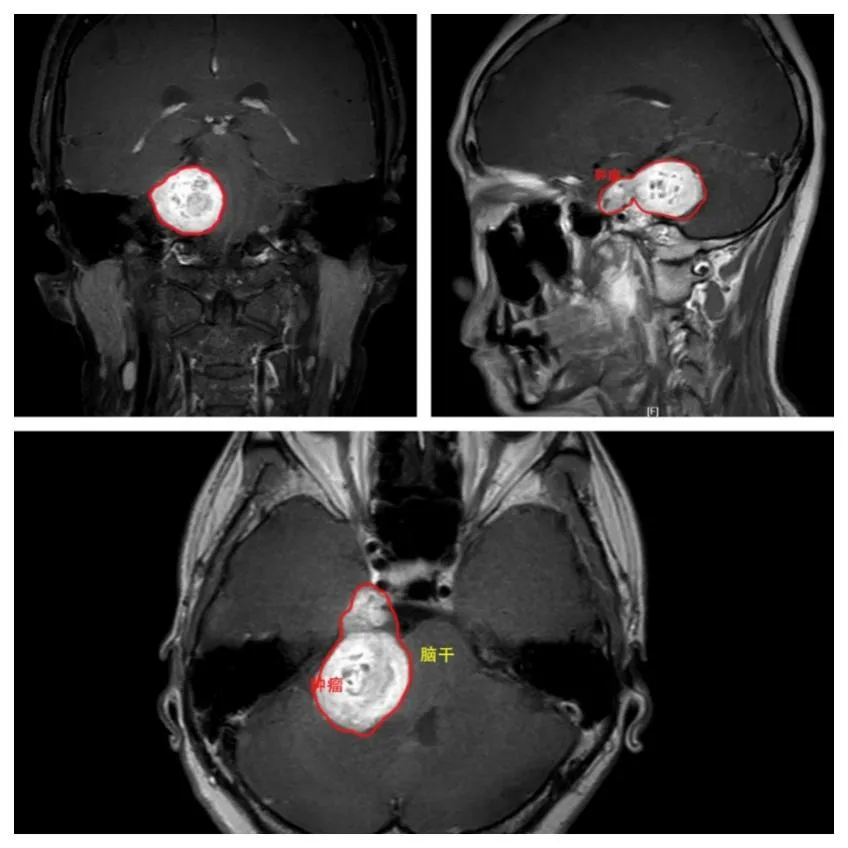

李女士此前多次求医,均被诊断为“典型三叉神经痛”,然而药物治疗却收效甚微。郭永川教授接诊后,凭借自身丰富的临床经验,敏锐地察觉到患者的症状存在“不典型” 之处。经过核磁共振检查,隐藏在背后的真相终于水落石出——原来李女士的三叉神经痛并非是常见的血管压迫所致,而是由一个直径约 3 厘米的巨大三叉神经鞘瘤引发的。

这个肿瘤情况颇为复杂:按照 Kawase 分型属于 mP 型,它同时累及颅中窝和后颅窝,且以后颅窝为主,还紧邻脑干、面听神经等重要结构,所处位置极为关键。三叉神经鞘瘤手术就像是在颅底岩尖这个神经血管最为密集、功能最为重要的 “生命禁区” 里进行的一场毫厘之间的精细 “刀尖舞蹈”,需要在保护脑干、面听神经等关键结构不受损的同时,精准完成肿瘤切除工作,必须做到全切肿瘤且保障神经功能完好,这无疑是一项巨大的技术挑战。

▲患者术前核磁共振检查